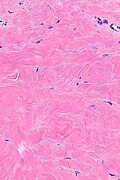

Microscopic

Features:[1]

- Septal fibrosis/expansion - key feature.

- Classically ~2-3x an adipocytes thick.

- +/-Deep dermal perivascular lymphocytes and plasma cells.